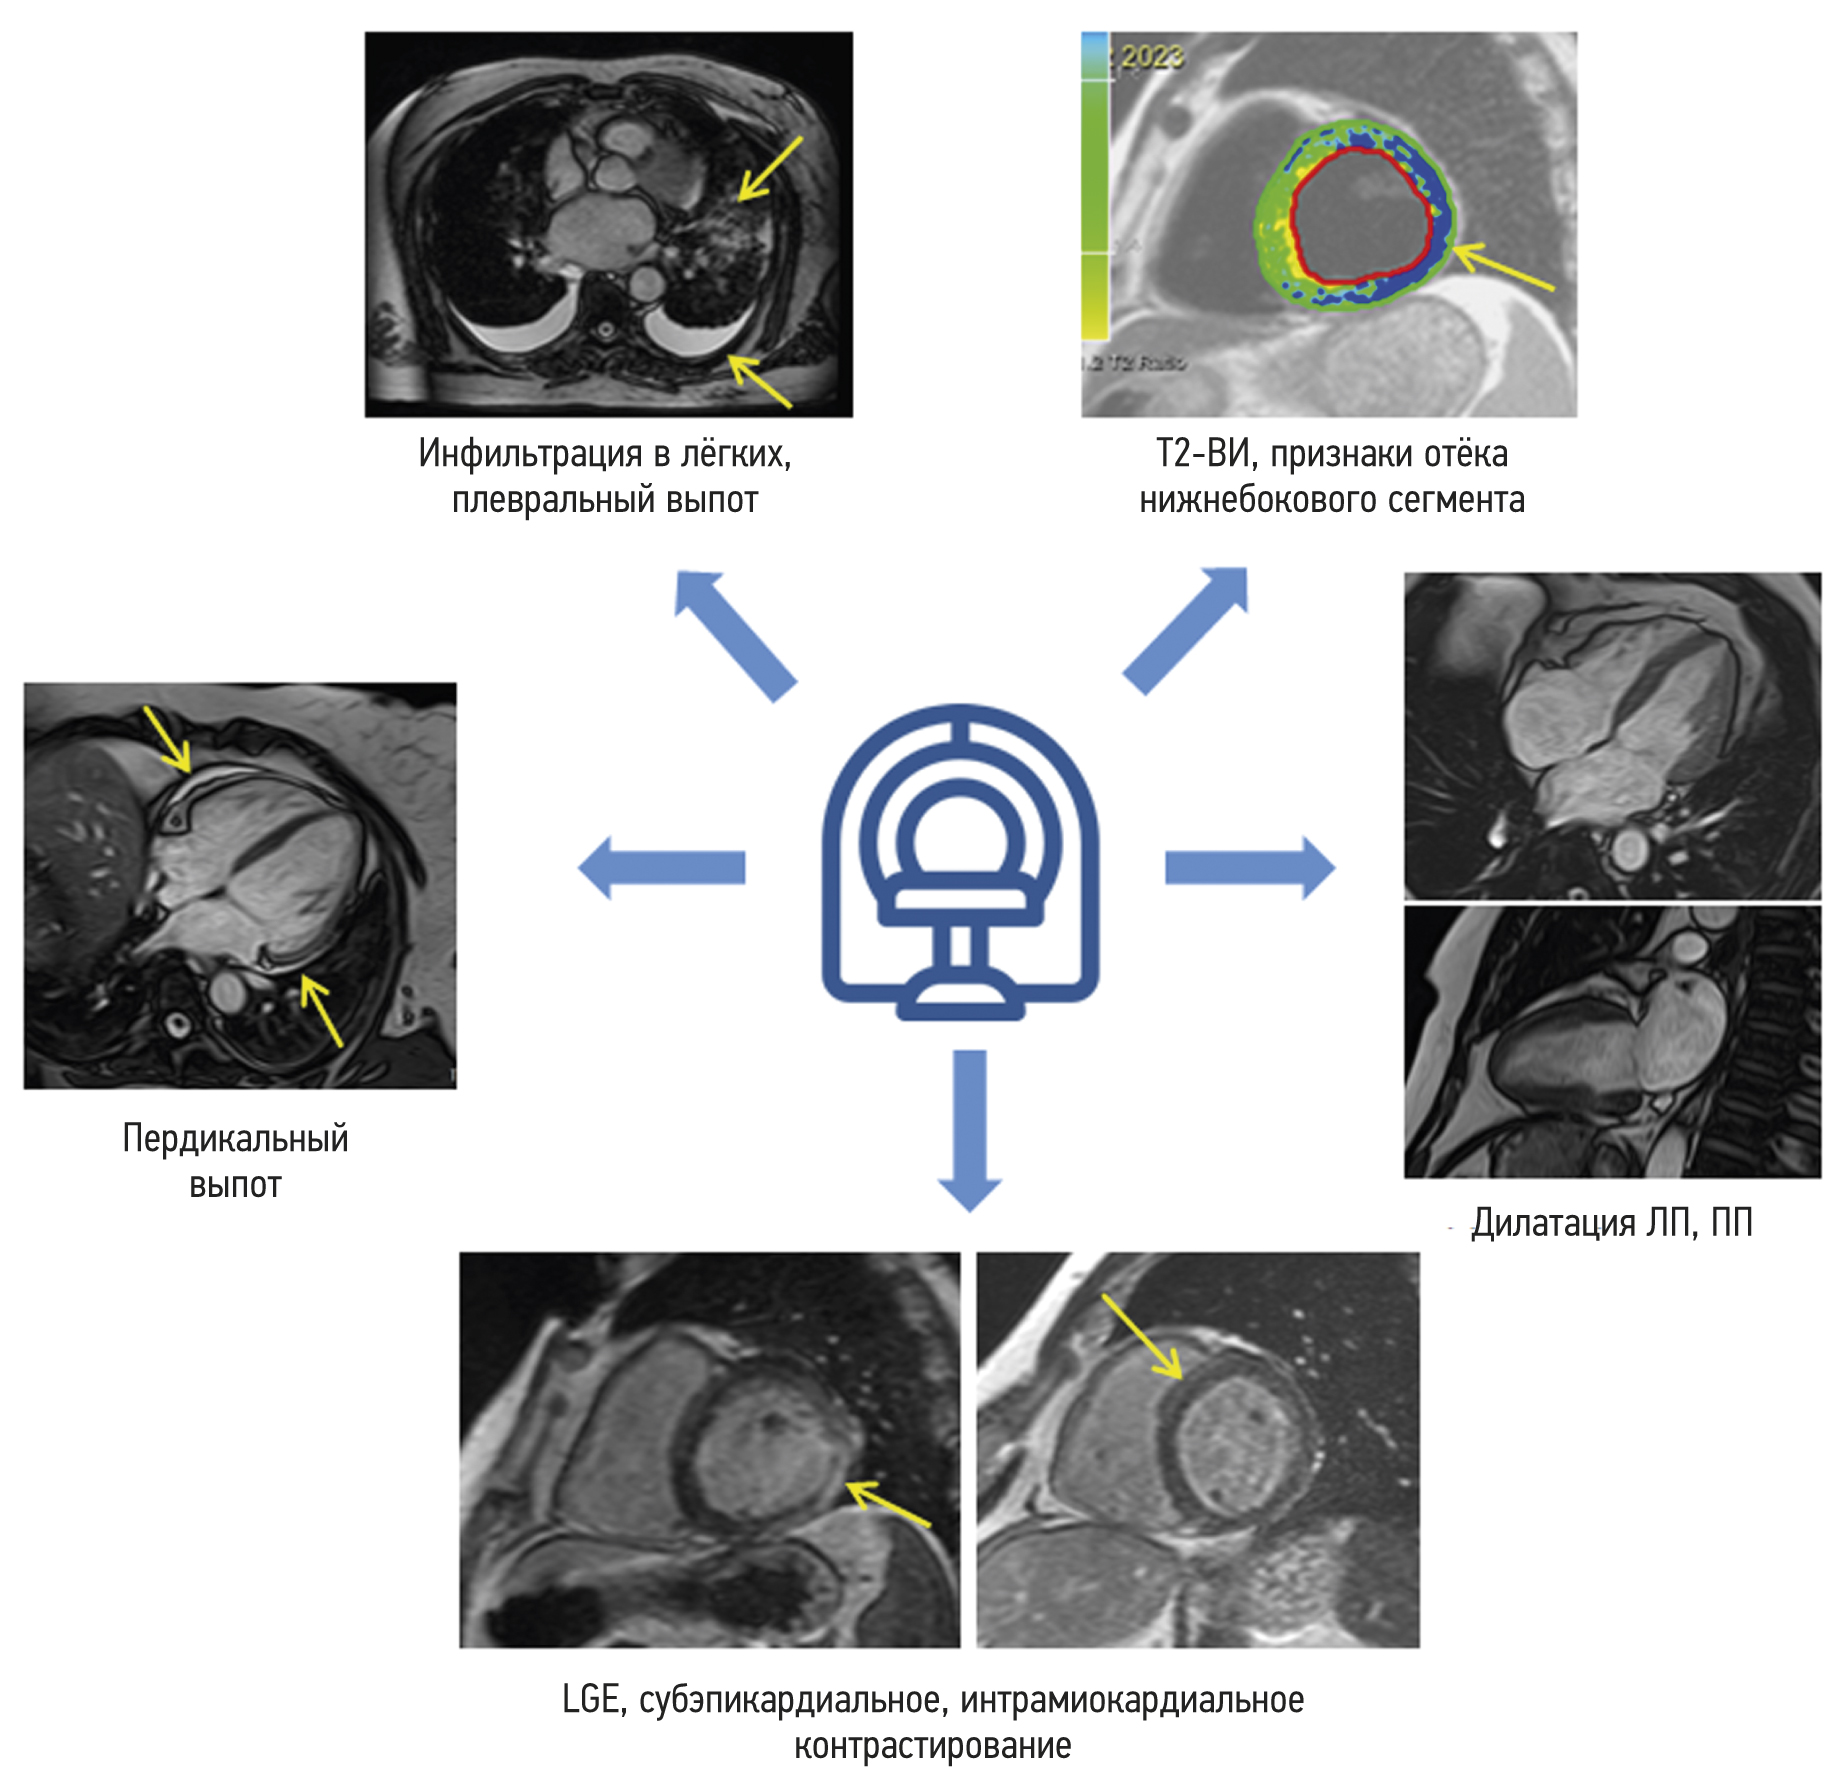

Cardiac magnetic resonance imaging in patients with history of COVID-19

BACKGROUND: Myocarditis is among the most common complications arising from coronavirus infection (COVID-19).

AIM: This study aims to find the differences in the patterns of myocardial injury between patients who had COVID-19 and those from the pre-pandemic period, as determined by contrast-enhanced cardiac magnetic resonance imaging.

MATERIALS AND METHODS: The study encompassed a retrospective analysis of 47 patients who underwent contrast-enhanced cardiac magnetic resonance imaging to rule out acute myocarditis. Group 1 comprised 34 patients with a confirmed history of COVID-19 through PCR testing (nasal and/or throat swabs), while Group 2 comprised 13 individuals who underwent contrast-enhanced cardiac magnetic resonance imaging in 2017 prior to the onset of the COVID-19 pandemic. All patients enrolled in the study had clinical manifestation of cardiac injury without signs of coronary artery disease as an underlying cause of condition.

RESULTS: The mean time from the onset of heart symptoms to the administration of contrast-enhanced cardiac magnetic resonance imaging was 166 days. In group 1, a decrease in exercise tolerance was observed in 77% of patients, and 14 (42%), 30 (88%), and 28 (85%) of patients complained of chest pain, shortness of breath, and heart palpitations, respectively. In group 2, four patients (30%) had dyspnea, nine patients (69%) complained of chest pain, and six patients (46%) had heart palpitations and/or feeling of arrhythmia. Myocardial injury in group 1 was more generalized. The third of them had displayed preserved increased pulmonary vascularity and pleural effusion. Within group 1, men had significantly lower left ventricular ejection fraction, lower values of global longitudinal deformation, and higher values of left atrial function compared with the corresponding parameters in women. Differences in women were found only in the number of the affected segments in the left ventricular myocardium.

CONCLUSION: SARS-CoV-2 virus caused extended myocardial injury, affecting a significant number of myocardial segments. Men had more frequent postinflammatory complications, characterized by abnormal function of the left ventricle and left atrium. Obtained results require continuous efforts for further assessment of long-term consequences of previous COVID-19 to the cardiovascular system. In this regard, contrast-enhanced cardiac magnetic resonance imaging may represent a sensitive imaging tool for the assessment of cardiac injury severity.